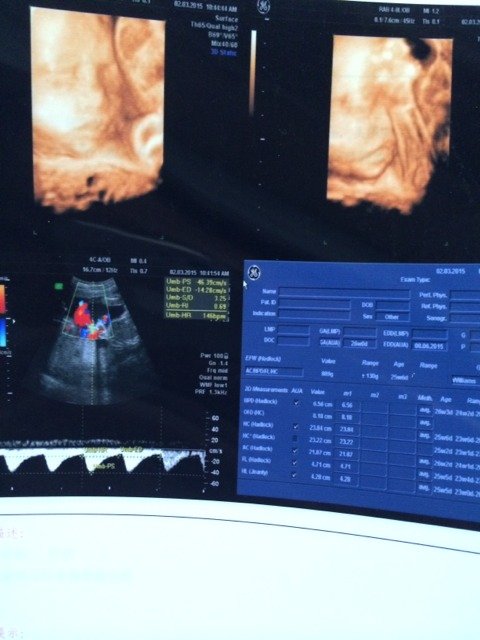

今天4围顺利回来,就是胎盘低了点,下怀,偏大一周,看的懂数据的宝妈门帮我看看是棉袄还是长腿尼,感谢

今天4围顺利回来,就是胎盘低了点,下怀,偏大一周,看的懂数据的宝妈门帮我看看是棉袄还是长腿尼,感谢😘😘😘带上照片和数据